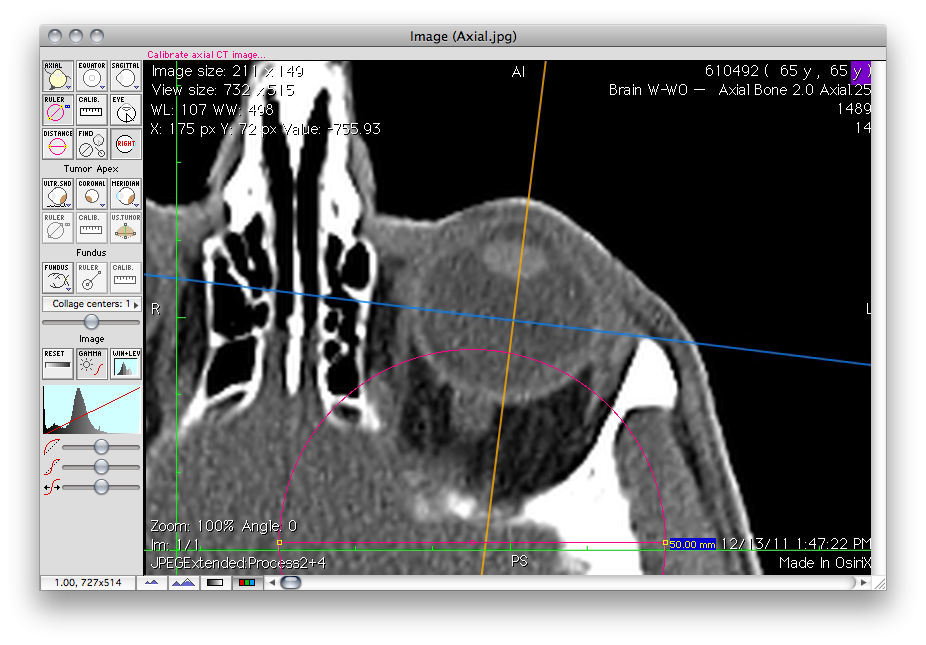

CT Calibration Tutorial

www.eyephysics.com

www.eyephysics.com

ct calibration ruler ps userguide ps5 eyephysics